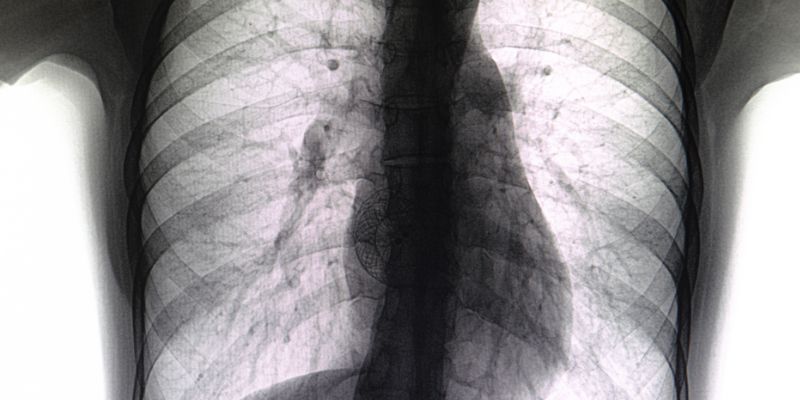

Σε αρκετούς ασθενείς παρατηρούνται υπερκοιλιακές αρρυθμίες στο ηλεκτροκαρδιογράφημά τους και στην ακτινογραφία θώρακος διακρίνεται διάταση του δεξιού κόλπου, της δεξιάς κοιλίας και των πνευμονικών αρτηριών, που είναι σοβαρές ενδείξεις παρουσίας μεσοκολπικού ελλείματος.